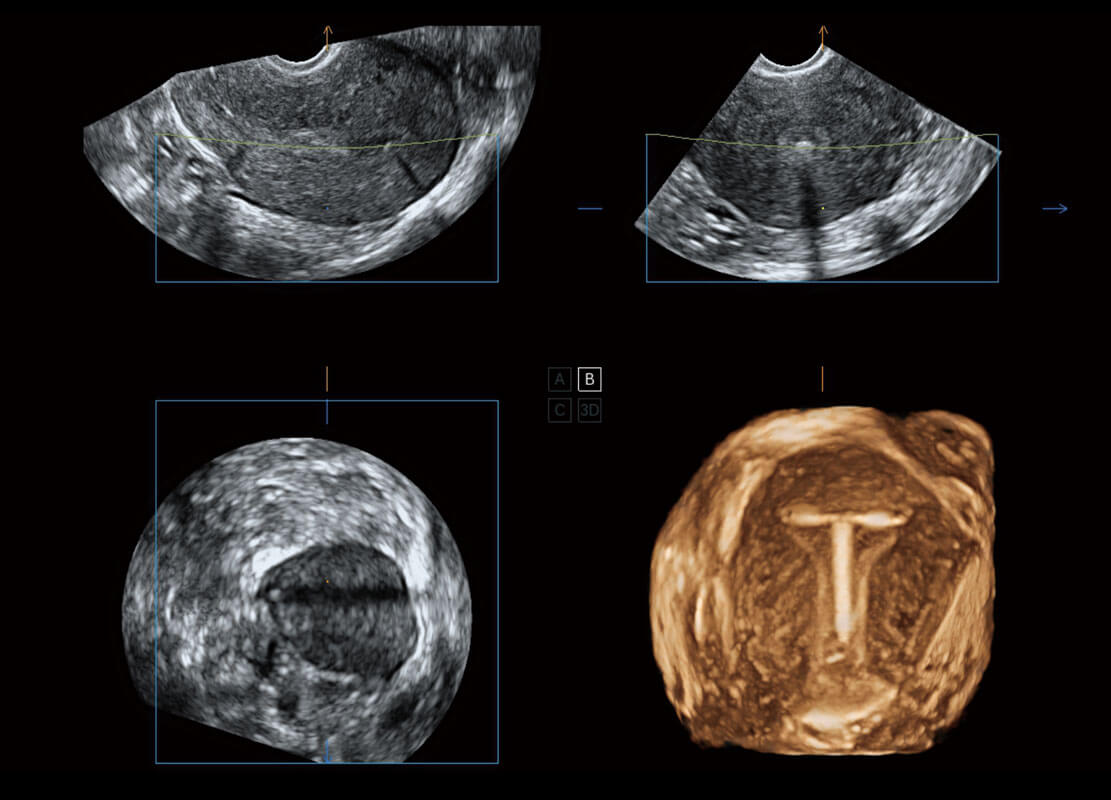

腔內(nèi)三維-宮內(nèi)節(jié)育器

P60優(yōu)異的圖像質(zhì)量搭載專(zhuān)科探頭,在婦科基礎(chǔ)疾病的診斷、卵泡生長(zhǎng)的監(jiān)測(cè)、輸卵管通暢情況的判別等方面為您提供生殖應(yīng)用方案。